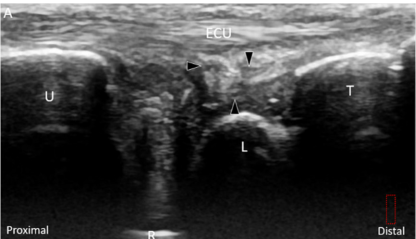

민트색 박스 표시한

척골 경상돌기(Sp)에 프로브를 대고

TFCC 장축 스캔을 하면요.

가장 바깥에

척측수근신근 힘줄이 보이고요.**

(ECU, extensor carpi ulnaris)

잘 보이시진 않겠지만

힘줄집(subsheath)을

신전근 지대(Extensor retinaculum)가

감싸고 있는 형태입니다.

@ DOI: 10.3390/jcm8101540

그 아래에 파란색으로 표시한

척골 측부인대(Ulnar collateral ligament)

가 보입니다.

그 아래는 빨간색으로 표시한

반월 연골 유사체(Meniscus homologue)

가 보이고요.

그 아래는 귤색으로 표시한

요척 인대(Radio-Ulnar ligament)

얕은층(superior limb)와

깊은층(deep limb)으로 보입니다.